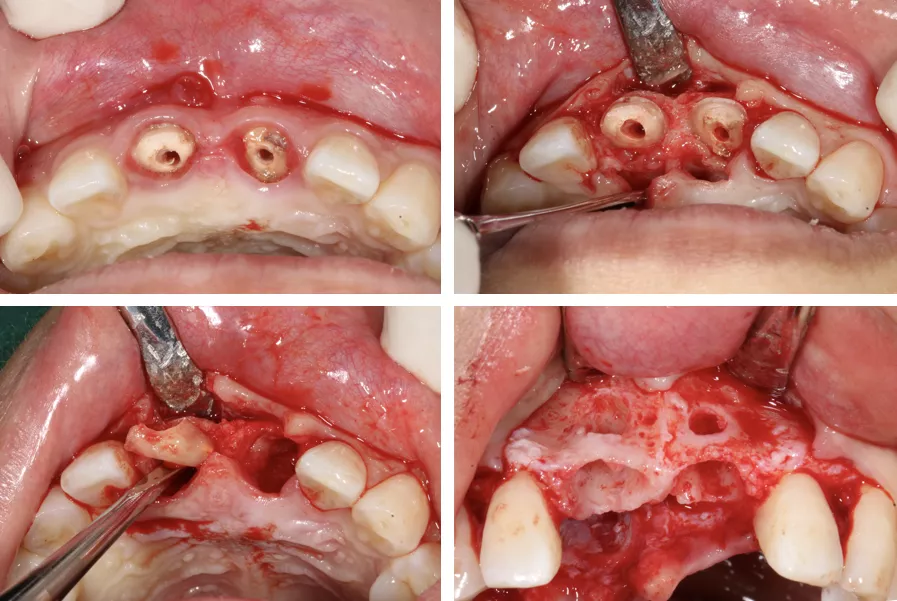

·      口内外消毒铺巾后,常规局麻下翻瓣,拔除患牙#11#21残根。

·      唇腭侧翻瓣显露牙槽骨壁。清整骨面后腭侧开窗,去除阻生埋伏多生牙。

·      采集自体血混合bio-oss骨粉0.75g植骨盖膜。

制作粘接固位临时修复体,基底部悬空。